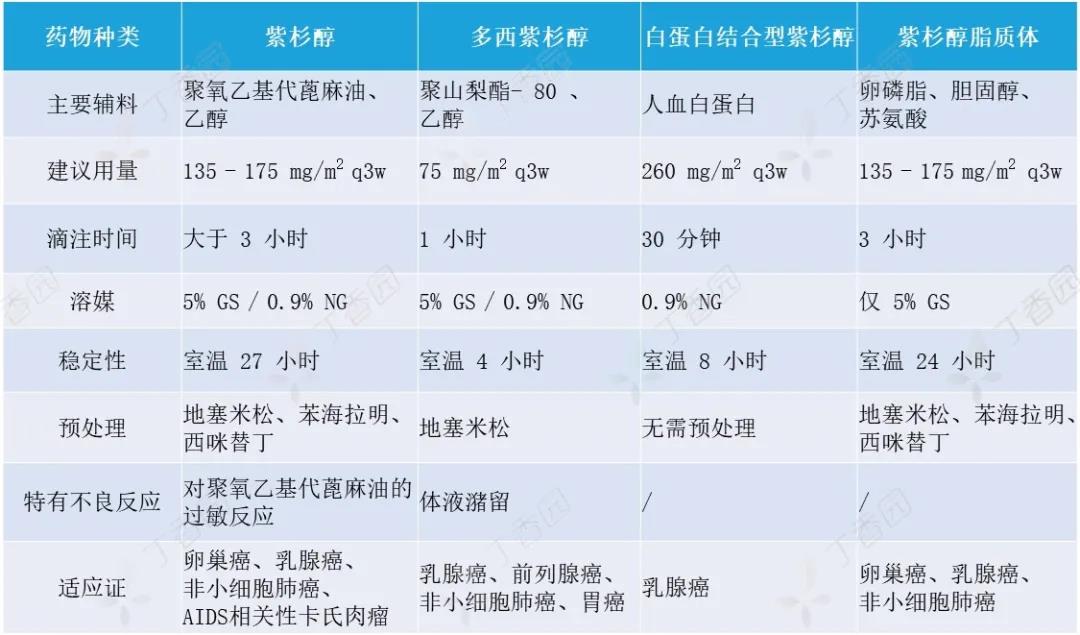

紫杉醇是一种新型抗微管药物,临床广泛用于卵巢癌、乳腺癌、肺癌、头颈部肿瘤、食管癌、胃癌及软组织肉瘤等。近些年来,通过对紫杉类药物的不断探索及制剂工艺的不断改进,目...